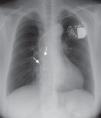

Case reportWe describe the case of a 50-year-old woman with a history of systemic lupus erythematosus (SLE) diagnosed in the second decade of life (1988), already with involvement of multiple organs and with previous hospital admissions because of disease complications, including lupus cerebritis and avascular necrosis of the femoral head. She was later diagnosed with symptomatic sinus dysfunction and underwent pacemaker implantation (DDDR mode) by the right subclavian route (1997). Three years after implantation there were signs of subcutaneous erosion in the pacemaker pocket and a surgical revision was performed with placement of a new generator. Three months after this procedure, a pacemaker pocket infection was detected and the system was explanted, except the atrial lead, which was sectioned and abandoned in the atrial cavity. A new system (AAIR mode) was implanted on the contralateral side (Figure 1). In the following eight years no pacemaker-related events occurred. She was admitted to the hospital with pulmonary thromboembolism in 2008. Her previous follow-up records showed that she had had several episodes of autoimmune disease exacerbation in recent years, with acute serositis and sicca syndrome, and was currently medicated with corticosteroids, hydroxychloroquine and azathioprine. She began oral anticoagulation with warfarin and was discharged uneventfully. In the following year she had three additional hospital admissions for recurrent segmental pulmonary embolism (diagnosed by CT angiography), although her INR was in the therapeutic range. All studies (including transthoracic echocardiograms) failed to show any embolic focus, but serological studies were positive for antiphospholipid antibodies. She was considered to have antiphospholipid syndrome associated with LES, which could explain the recurrent thromboembolism. The oral anticoagulation dosage was increased and she remained free of new events in the following year. In the meantime, a new pacemaker generator was placed because of battery depletion, without complications. In July 2010, during a routine follow-up in the autoimmune clinic, she complained of pain and swelling in the right arm. She had elevation of inflammatory markers and Doppler echocardiography showed decreased pulsatility in the right brachiocephalic trunk, which was suggestive of subclavian vein thrombosis. Inflammatory marker levels continued to rise in the following weeks, with all microbiological exams negative and normal scintigraphy with marked leukocytes. As part of the study, a new transthoracic echocardiogram was performed that showed two masses in the right atrium adherent to a pacemaker lead, with a high degree of motility, one of them prolapsing into the right ventricle during diastole (Figure 2). A diagnosis of pacemaker endocarditis was made and the pacemaker system was extracted surgically and an epicardial pacemaker system was implanted. The histopathological analysis of the masses (Figure 3) was compatible with vegetations. Nevertheless, cultures of the removed material were negative for bacteria and all previous blood cultures were negative, with incubation periods exceeding two weeks. She was started on an antibiotic regimen after the surgery, but this was rapidly suspended because of the negative microbiological results. New blood cultures were collected at different intervals, including some specific for fungi, that were also negative. All the serological tests, including those specific for viruses, Brucella, Bartonella and Coxiella, were also negative. On the basis of these findings, it was proposed that she had NBTE associated with her autoimmune disease and not a bacterial infection. The patient maintained her usual immunosuppressant drugs and oral anticoagulation, and no additional course of antibiotics was prescribed. She remained clinically well, with no further events, with decreasing levels of inflammatory markers and normal postoperative transthoracic and transesophageal echocardiograms.